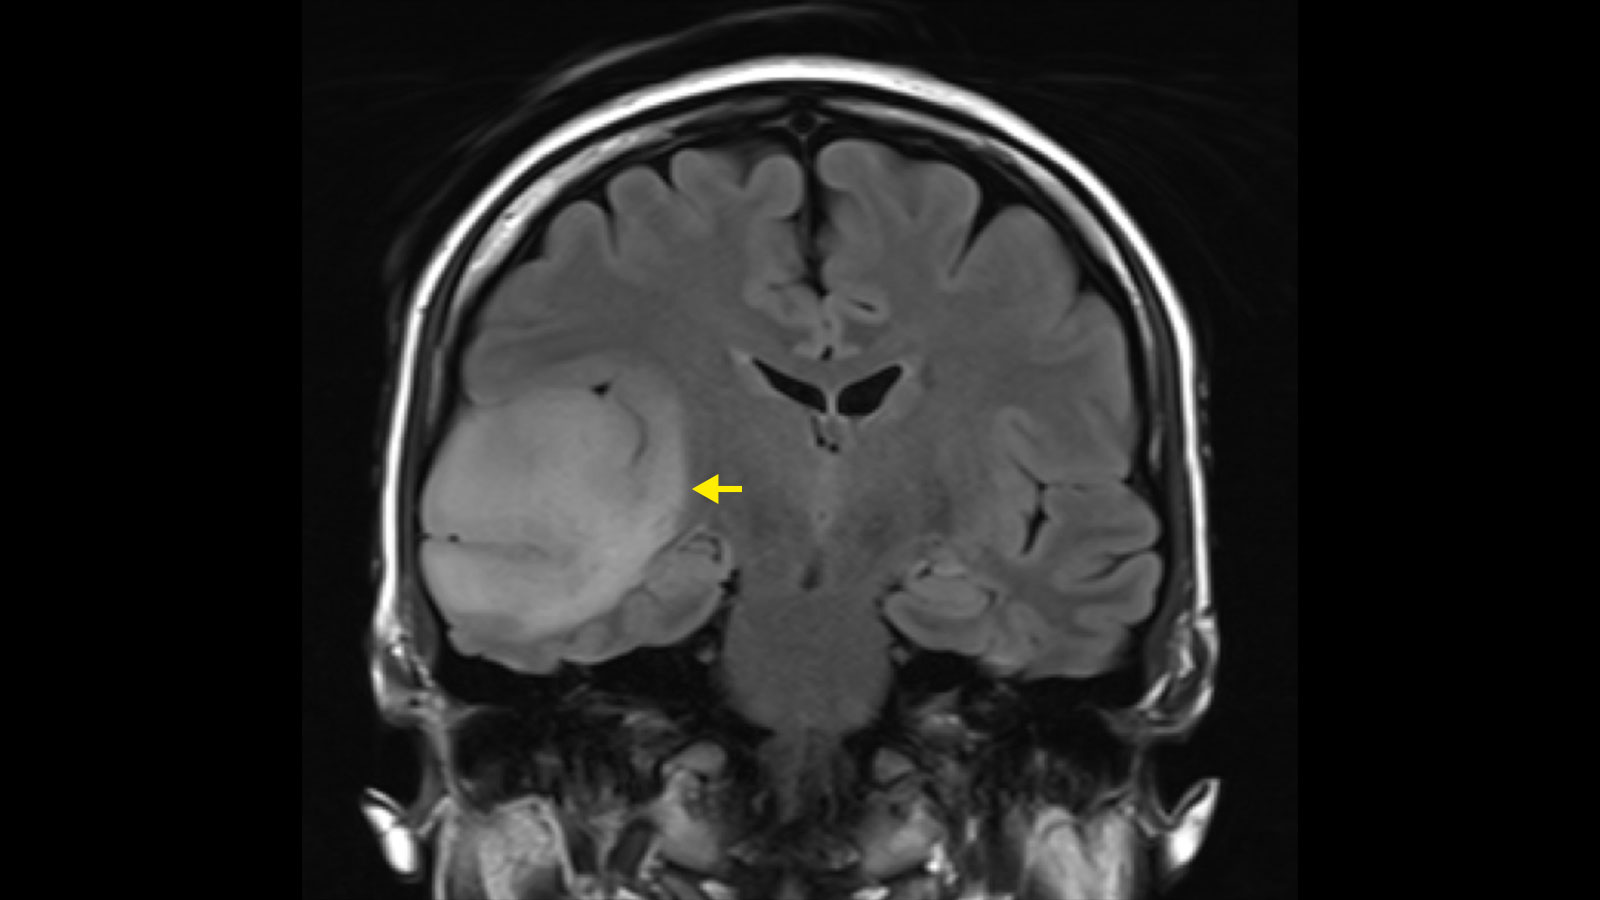

Locating Tumors

A brain MRI provides precise information about a tumor’s location. Specialists analyze the images to pinpoint the exact area of concern within the brain’s intricate geography. Knowing the specific location is a primary step, and the MRI scan provides this data with high accuracy. The scan creates a detailed map, which helps guide the next steps in your medical care.

These detailed images help doctors understand the tumor’s relationship to surrounding brain structures, and this information is helpful for planning. To do this, the scan shows if the mass is near areas that control speech, movement, or other functions. Medical teams use these details to develop a careful approach for you.

An MRI scan is also useful for assessing the extent of a tumor; the images show whether the mass has clear or irregular borders. A tumor with well-defined edges may be easier to distinguish from healthy tissue, whereas one with indistinct borders suggests infiltration into nearby areas. Doctors examine these boundaries to understand the tumor’s behavior.